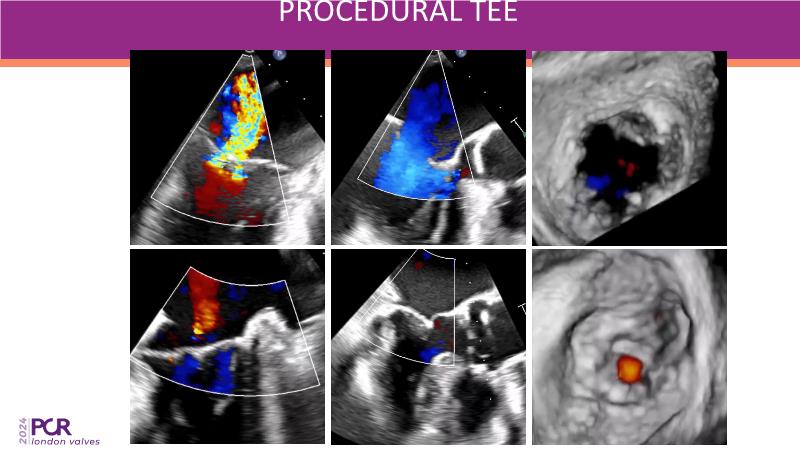

This session on mitral regurgitation offers an in-depth look at the EMPOWER trial outcomes, indirect annuloplasty in aFMR, and remodeling with the CARILLON device. Explore the benefits of early treatment for secondary mitral regurgitation, understand the role of left ventricular reverse remodeling, and review the latest clinical evidence supporting indirect annuloplasty. Discover how this technique keeps future treatment options open while expanding therapeutic possibilities for aFMR.

- To hear the latest clinical evidence concerning indirect annuloplasty using the CARILLON device